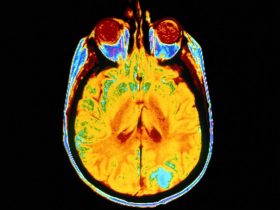

WEDNESDAY, July 24, 2024 (HealthDay News) — Sexual and gender minority adults in the United States have a disproportionate prevalence of epilepsy, according to a study published online July 22 in JAMA Neurology.

The researchers found that active epilepsy was present in 1.2 percent of the population, overall. A higher proportion of sexual and gender minority adults reported active epilepsy (2.4 percent, versus 1.1 percent in non-sexual and gender minority adults). When adjusting for age, race, ethnicity, income, and education, the odds of epilepsy among sexual and gender minority people was more than doubled (adjusted odds ratio, 2.14).